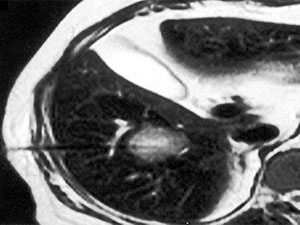

Вивчення біоптату (зразка тканин печінки) дає інформацію, яка дуже важлива як для пацієнта, так і для лікаря, і дозволяє прийняти рішення про необхідність і тактику противірусної терапії. У процесі біопсії за допомогою спеціальної голки отримують шматочок печінки діаметром близько 1 мм і довжиною близько 1,5-2 см. Процедура проходить під місцевим знеболенням і під контролем УЗ, так, що лікар, що проводить дослідження, може контролювати хід голки. Це дозволяє зробити маніпуляцію безпечною, тому що виключає можливість пошкодження судин і жовчних ходів.